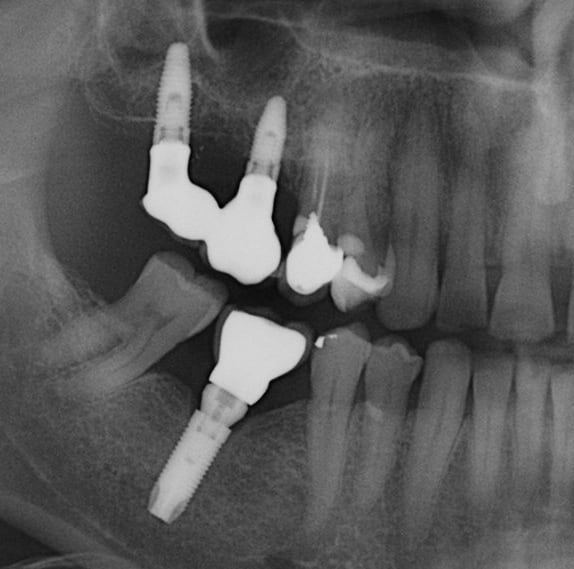

L'image de l'implant qui a cassé en apical, reprise quelques temps après avec une scie cloche, repose et radio à 5 ans.

Malgré une adaptation prothétique inadéquate, pas de gros problème.

Je précise qu'avant la "fracture" de l'implant, la résorption osseuse allait jusqu'à la partie cassée.

Ce qui est étonnant dans ce cas, c'est que le patient implanté dans les années 96, a perdu ses 3 ou 4 implants (je n'ai pas la fiche) pour cause de peri-implantite (ma première) et ce aussi bien sur du cylindrique que sur du Tatum D4 (20mmx 7 x 4.5)donc avec très gros dégâts à la dépose, et malgré ça le patient voulait du fixe, j'ai ré-implanté ( 6 implants) et plus aucun problème depuis ...

à le patient fumait... 2 à 3 cigarettes / jour et ne fume plus maintenant...